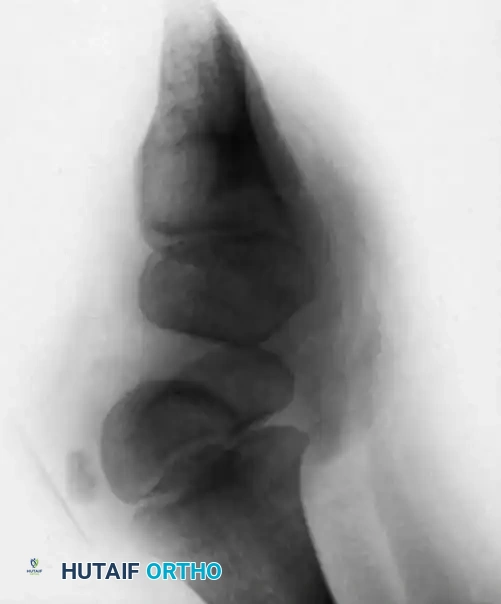

Clinically, the involved leg is significantly shortened. The fibular head is often palpable, particularly if it is proximally displaced into the popliteal fossa. The foot is typically held in severe, rigid equinovarus, and the hindfoot is profoundly stiff.

In older children, the proximal tibial anlage may be palpable upon deep clinical examination, even if it is not radiographically visible. The knee is generally flexed, and in more severe deformities, profound quadriceps insufficiency causes an absolute lack of active knee extension.

Classification of Tibial Hemimelia

The most widely utilized and surgically relevant classification scheme for tibial hemimelia is that of Jones, Barnes, and Lloyd-Roberts. This system is based on early radiographic presentation and directly guides treatment recommendations.

- Type 1A Deformity: There is complete radiographic absence of the tibia and a hypoplastic distal femoral epiphysis compared with the contralateral normal side.

- Type 1B Deformity: There is no radiographic evidence of an ossified tibia; however, the distal femoral epiphysis appears more normal in size and shape. This distinction is critical because Type 1B deformities possess a proximal tibial cartilaginous anlage that can be expected to ossify over time. Modern imaging techniques, such as high-resolution ultrasound and MRI, are mandatory to identify this cartilaginous anlage.

- Type 2 Deformity: A proximal tibia of varying size is present and ossified at birth. The fibula is usually normal in size, but the fibular head is proximally dislocated.

- Type 3 Deformity: The proximal tibia is not radiographically visible, but the distal tibial epiphysis is present. This is an exceptionally rare variant. The distal femoral epiphysis is usually well-formed, but the upper end of the fibula is proximally dislocated, leading to profound knee instability.

- Type 4 Deformity: The tibia is shortened, and there is proximal migration of the fibula with distal tibiofibular diastasis. This rare deformity is also referred to as congenital diastasis of the ankle joint. The distal tibial epiphysis may be entirely absent.